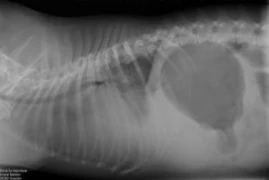

Sichtbar - der praxisorientierte Röntgenkurs nach Leitsymptomen

Ganz nach dem Motto: “Man sieht nur, was man kennt” werden in diesem Kurs in 5 on-demand Webinaren Röntgenbilder nach Leitsymptomen besprochen. Ziel ist es, die Anzahl an sichtbaren Informationen pro Aufnahme zu erhöhen.Referenten:Innen Kristina Lederer, Penelope Baloi, Beate Katharina Bosch -